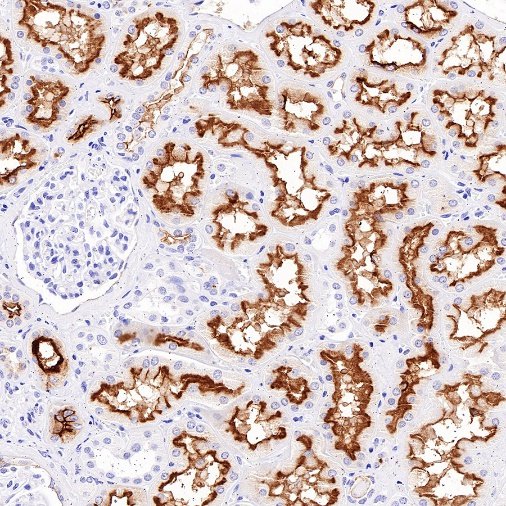

Immunohistochemistry

IHC shows positive staining in paraffin-embedded human kidney. Anti-MDR1/ABCB1 antibody was used at 1/1000 dilution, followed by a HRP Polymer for Mouse & Rabbit IgG (ready to use). Counterstained with hematoxylin. Heat mediated antigen retrieval with Tris/EDTA buffer pH9.0 was performed before commencing with IHC staining protocol.